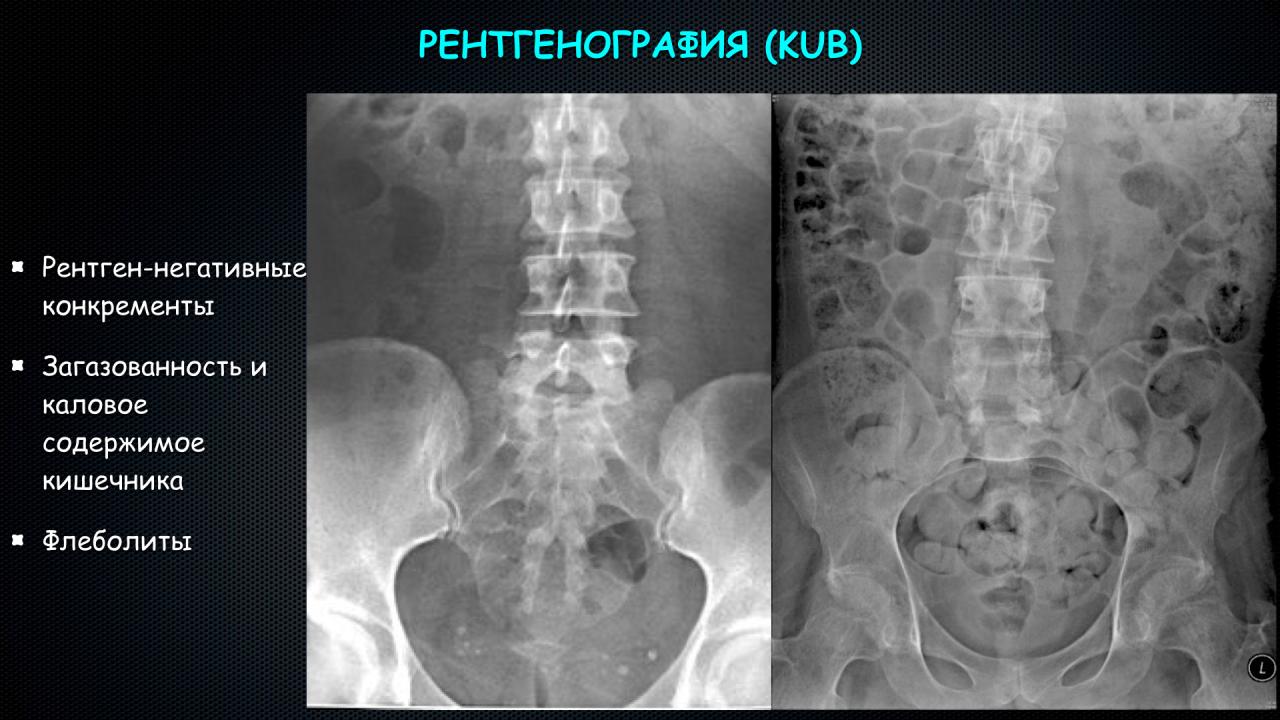

Медицинские изображения: Обзорная рентгенография урография

Раздел: Фокус на знании